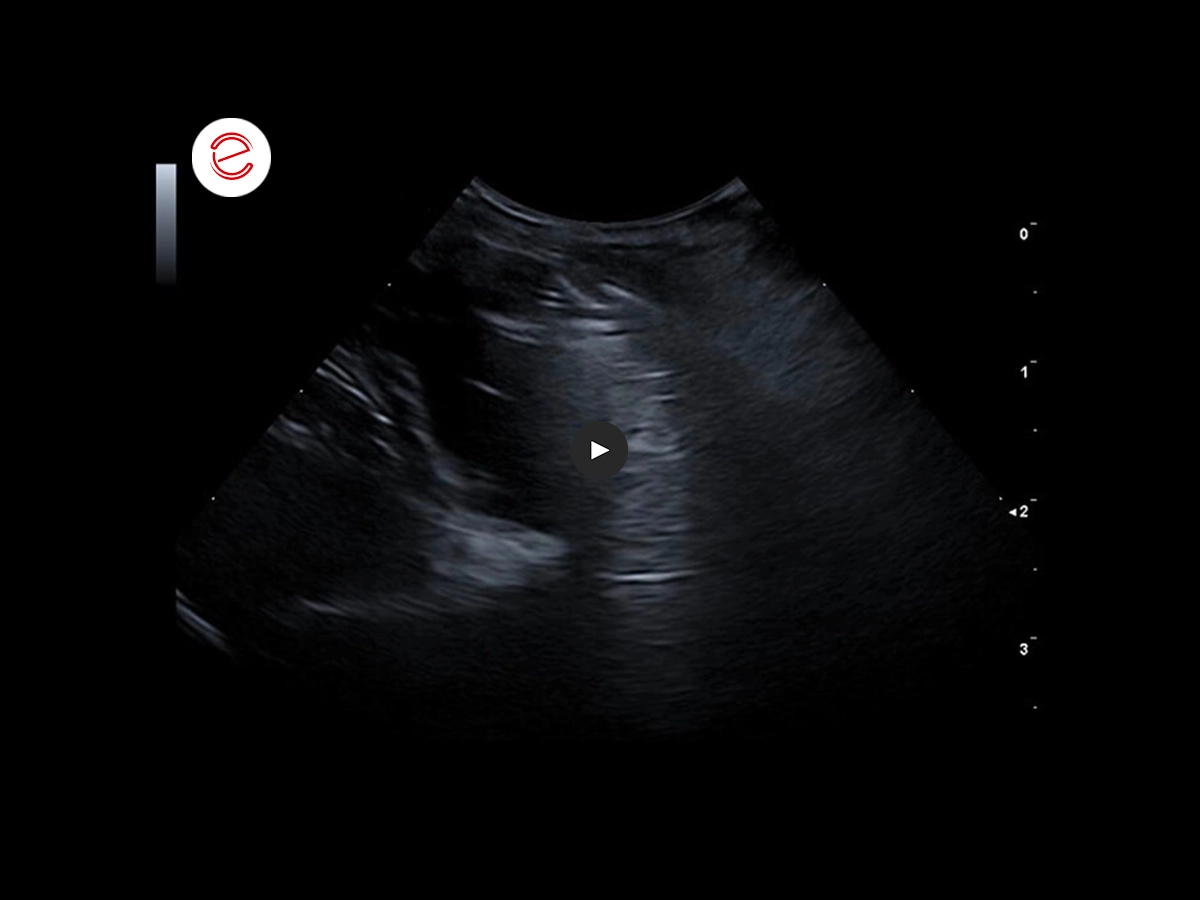

Ecografia del fegato

L'esame ecografico del fegato ha evidenziato un pattern ecogeno aumentato e non omogeneo.

È stata quindi eseguita una biopsia epatica.